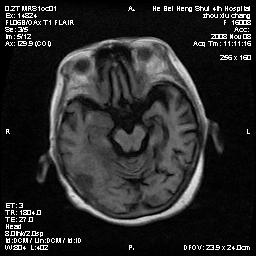

标题: MRI1883:女67岁,半年前曾患脑梗塞,治疗后好转,近3各月精 [打印本页]

标题: MRI1883:女67岁,半年前曾患脑梗塞,治疗后好转,近3各月精

女67岁,半年前曾患脑梗塞,治疗后好转,近3各月精神恍惚。

两种可能:1,转移瘤,2,脑炎,建议增强扫描

多发硬化(年龄不太支持)待排转移瘤

转移瘤?淋巴瘤?

形态及整体病灶看起来首先考虑转移瘤或淋巴瘤,但奇怪的是多个病灶周围均未见显著的水肿区,这不符合这两个肿瘤的特点,结合ct表现及患者病史有个人考虑是否有皮层下动脉硬化性脑病伴多发胶质增生可能.

考虑  皮层下动脉硬化性脑病伴脑炎或

不像占位性病变,考虑脱髓鞘改变

脑转移瘤?

1皮层下动脉硬化性脑病,2胶质增生。

皮层下动脉硬化性脑病伴脱髓鞘改变!

脑白质病

不除外转移瘤,建议增强

支持:皮层下动脉硬化性脑病伴脱髓鞘改变。